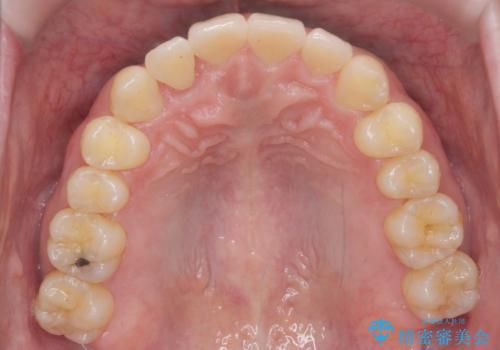

引っ込んだ前歯を並べる 歯を抜かないマウスピース矯正

- 右上の前歯が内側に入っているのを気にして来院。

右上の奥歯を後ろに移動して、前に出すスペースを確保してから並べました。

奥歯を後ろに送るために、矯正用インプラントを使用しています。

口を開けたとき、笑顔の印象が大きく変わり、大変喜んでいただけました。